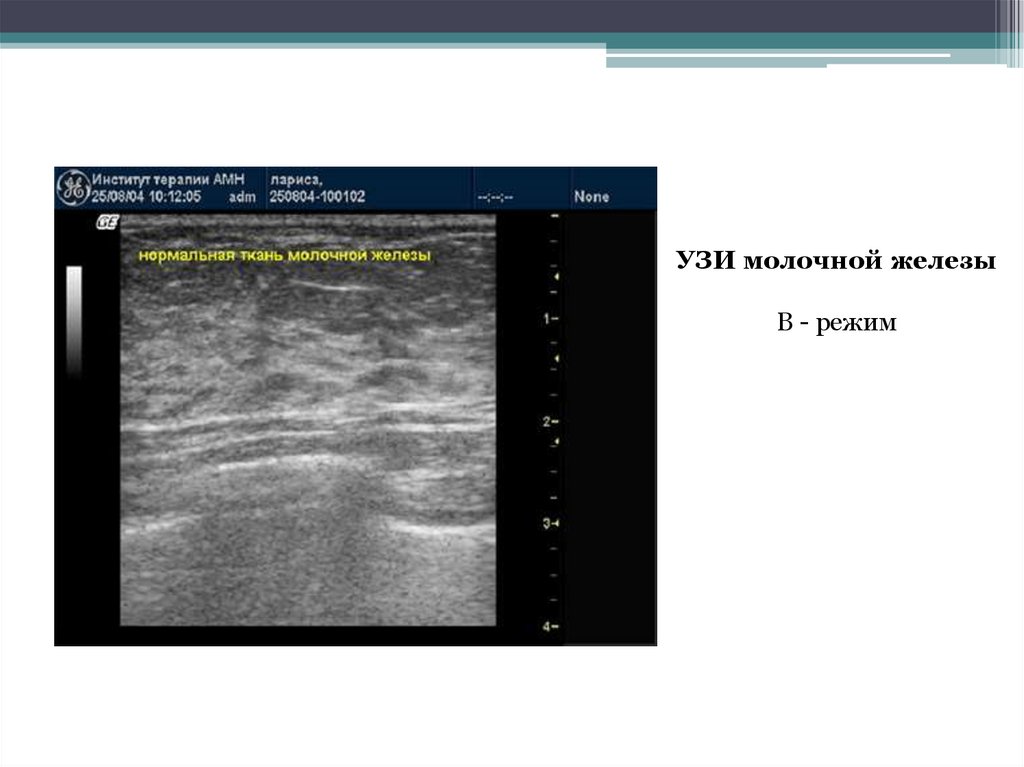

УЗИ молочной железы

В - режим